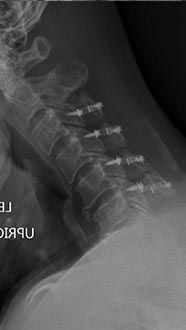

61 year old man with previous history of microdiscectomy at L4-5 presenting with severe back pain with radiating pain down the right leg with weakness. He had a massive disc extrusion on the right side. Options included revision discectomy vs. L4-5 revision decompression and fusion with transforaminal lumbar interbody fusion (TLIF). Patient did not want to go through the pains of recurrent disc herniation again and elected for the fusion.